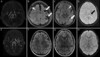

• AVC detectado por TC ou RNM que não é lacunar

Infarto subcortical na distribuição das pequenas artérias cerebrais penetrantes cuja maior dimensão é ≤1,5 ​​cm na TC ou ≤2,0 cm em imagens de difusão de RNM

● O infarto superficial isolado sugere um mecanismo embólico de uma grande artéria, coração ou aorta

Infartos corticais ou grandes subcorticais em múltiplos territórios vasculares sugerem uma fonte proximal de embolia do coração ou da aorta

Infartos de idade variável em um único território vascular sugerem uma grande fonte de embolia arterial

●Infartos em áreas de fronteira sugerem que o mecanismo do AVC é baixo fluxo (hipoperfusão) ou pequenos êmbolos múltiplos

● Pequenos infartos subcorticais sugerem infarto lacunar de doença de pequenos vasos

Doença cerebrovascular progressiva crônica caracterizadas por estenose bilateral ou oclusão das artérias ao redor do círculo de Willis com circulação colateral arterial proeminente. * A doença de Moyamoya: pacientes com achados angiográficos de moyamoya que podem ter suscetibilidades genéticas, mas sem fatores de risco subjacentes. * A síndrome de Moyamoya: pacientes com achados angiográficos de moyamoya que também apresentam uma condição médica associada. **Apresentações clínicas** – O acidente vascular cerebral isquêmico e o ataque isquêmico transitório (AIT) que afetam a circulação anterior são as apresentações clínicas mais comuns. A hemorragia intracraniana é menos comum e rara em crianças, geralmente afeta estruturas profundas, como os gânglios da base ou o tálamo, mas também pode ser intraventricular ou subaracnóidea Os achados de ressonância magnética que sugerem o diagnóstico de moyamoya incluem dilatação colateral dos vasos nos gânglios da base ou tálamo, o **"sinal da hera" ou o "sinal do pincel".** Dx: demonstração angiográfica de estenoses bilaterais que afetam as artérias carótidas internas distais ou o círculo proximal dos vasos de Willis, juntamente com a presença de vasos colaterais basais proeminentes